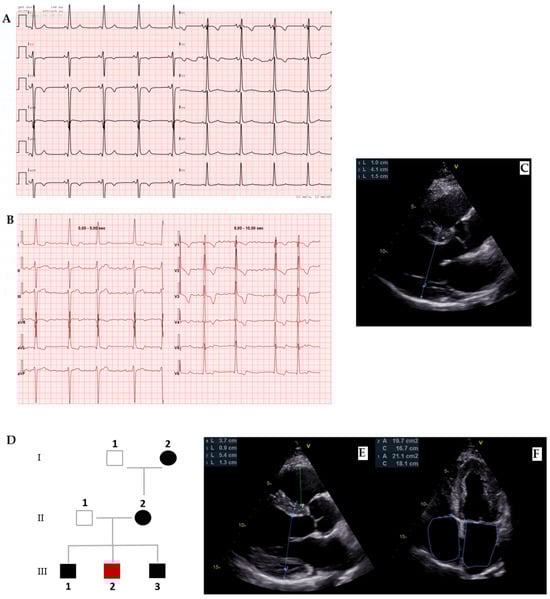

The clinical presentation of PRKAG2 syndrome can vary widely, with some patients displaying mild ventricular hypertrophy and arrhythmias, while others may be asymptomatic or at risk of SCD. In some cases, the syndrome may progress to heart failure (HF) or involve other systemic manifestations. The most frequently observed electrocardiographic finding is ventricular pre-excitation (Figure 7A), which appears in over half of the patients, often accompanied by bundle branch block, particularly affecting the right bundle. This seems to be related to both glycogen-induced structural remodeling of the AV junction and conduction system, favoring the development and unmasking accessory pathways. Additionally, slurred QRS complexes and atypical patterns of intraventricular conduction delays have been noted. Advanced atrioventricular or sinoatrial blocks are also commonly seen, as well as early-onset atrial fibrillation. High-voltage QRS complexes with secondary repolarization abnormalities frequently occur, even in the absence of echocardiographic left ventricular hypertrophy (Figure 7). Even if the most frequent arrhythmic problems are supraventricular arrythmias, characteristically this syndrome leads to advanced AV blocks, marked sinus bradycardia, or sinus blocks, even within the third or fourth decade of age: these conditions lead to pacemaker implantation in more than 40% of patients observed. Cardiac hypertrophy predominantly affects the left ventricle, characterized by a symmetrical and progressive nature, often accompanied by both diastolic and systolic dysfunction (Figure 7) [53]. Although the maximum ventricular wall thickness can vary and may be significant, it is infrequently associated with left ventricular outflow tract obstruction [54]. However, a restrictive mitral inflow Doppler pattern, hemodynamically significant left ventricular outflow tract obstruction, and progressive dilation could be major contributors to the need for cardiac transplantation or SCD. Additionally, no specific patterns related to cardiovascular magnetic resonance imaging have been identified in association with this syndrome [54,55]. Extracardiac involvement is rare and could determine skeletal myopathy and arterial hypertension.

Figure 7. PRKAG2 disease. (A) Forty-one-year-old male diagnosed with PRKAG2 syndrome because of ventricular pre-excitation, (B) paroxysmal atrial fibrillation, and (C) cardiac hypertrophy in young age as red flags. (D) The definitive diagnosis was confirmed by genetic testing (p.Arg302Gln mutation). Family screening with ECG and echocardiography was initiated from the proband (II-2) and led to early diagnosis in two brothers, as well as in the mother and maternal grandmother, demonstrating an autosomal dominant transmission of the mutation. (E,F) Echocardiogram of III-3, a 36-year-old male showing early cardiac hypertrophy.